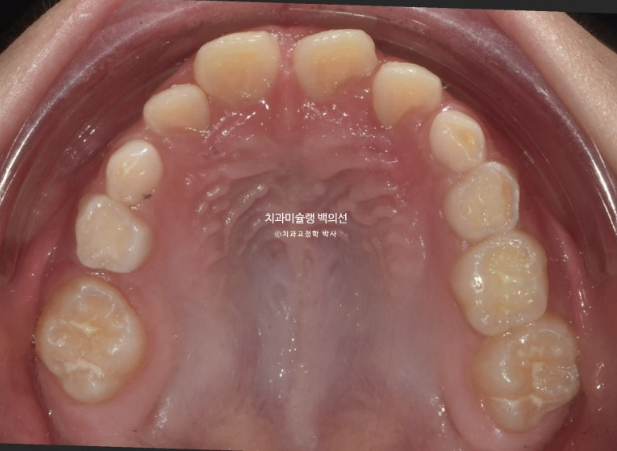

2025.5 드디어 치료를 마무리 했습니다.

중심선은 잘 맞으며

그사이 남은 유치들이 대거 빠지고 영구치 맹출을 기다리는 중입니다.

비대칭은 개선되었으며 중심선은 맞아졌습니다.

앞니 교합은 좋습니다.